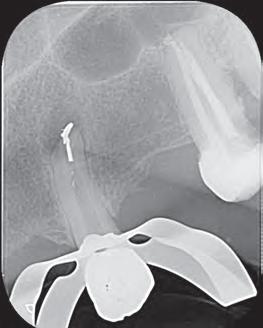

Caso clínico

Paciente del género femenino, 44 años de edad, asistió al consultorio para realizar el retratamiento endodóntico del diente 22. Hemos hecho la radiografía inicial para evaluar el diente 22 y nos encontramos con una imagen radiolúcida en forma de globo, caracterizando una reabsorción radicular interna en el diente 21. Hemos hecho, entonces, una nueva radiografía para evaluar el diente 21 (Figura 1).

Figura 1 - Radiografia inicial

Durante la anamnesis la paciente relató haber sufrido un cabezazo del hijo hace dos años. El examen clínico reveló presencia de faceta de porcelana en el diente 21, prueba de sensibilidad pulpar positiva, ausencia de sintomatología y ausencia de alteraciones en la mucosa gingival. Solicitamos una tomografía computarizada cone beam (Figuras 2, 3 y 4) para confirmar el diagnóstico, evaluar si la reabsorción era comunicante o no y para estudiar la estructura dental radicular remanente.

Después del análisis clínico, radiográfico y tomográfico, se estableció el diagnóstico de reabsorción radicular interna, sin comunicación externa, lo que hace el pronóstico más favorable.

En la segunda sesión, 15 días después, realizamos la obturación convencional del tercio apical del canal con gutapercha, llenado de la cavidad reabsortiva con BIO-C ® REPAIR (Angelus, Londrina - Brasil) (Figura 7, 8 y 9), condensándolo contra las paredes con condensadores específicos y bolita de algodón humedecida y realizamos el sellado coronario con resina.

8 - Radiografia final